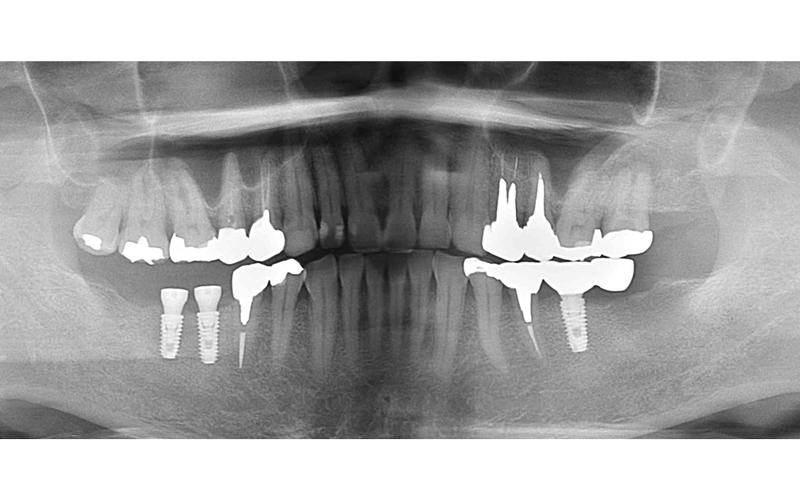

左下インプラント埋入

右下インプラント埋入

| 備考 | 【治療詳細】 右下の6番延長ブリッジの根が太く長い土台の金属が入っており、歯根破折しておりました。 左側の7番も同様に歯根破折しておりました。 左側インプラント治療後。患者さん希望の為、インプラント体1本に対して2本分の被せ物で補綴。 案の定、内部のネジの緩みが何度か発生。 右下が保存不可能になった為、インプラント2本埋入。 右下のインプラントが経過良く、左下のインプラントの追加を希望されましたので、被せ物をいったん除去して追加埋入。 補綴完了後の口腔内。現在最初のインプラント埋入から5年経過しておりますが、経過良好です。 左下6番のみ被せ物の内部に金属を使用していますが、他はフルジルコニア。 アクセスする穴にレジンを使用しています。 |